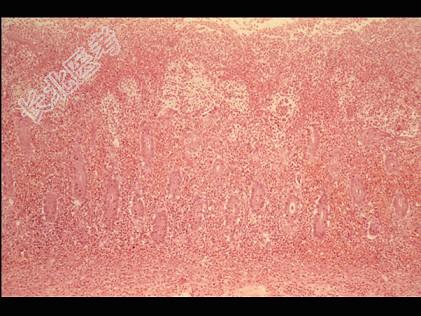

- 多项选择题根据图,关于菌痢的病理改变正确的是 ( )

A、黏膜充血、水肿、中性粒细胞和巨噬细胞浸润

B、黏膜下层、肌层、浆膜层有明显的炎症反应

C、假膜主要为纤维素、坏死的肠黏膜、细菌、嗜中性粒细胞及红细胞等,部分有脱落

D、整个肠黏膜有假膜覆盖,黏膜上皮及腺体大片消失

E、大约一周左右,假膜开始脱落,形成大小不等,形状不一的“地图状”溃疡如图